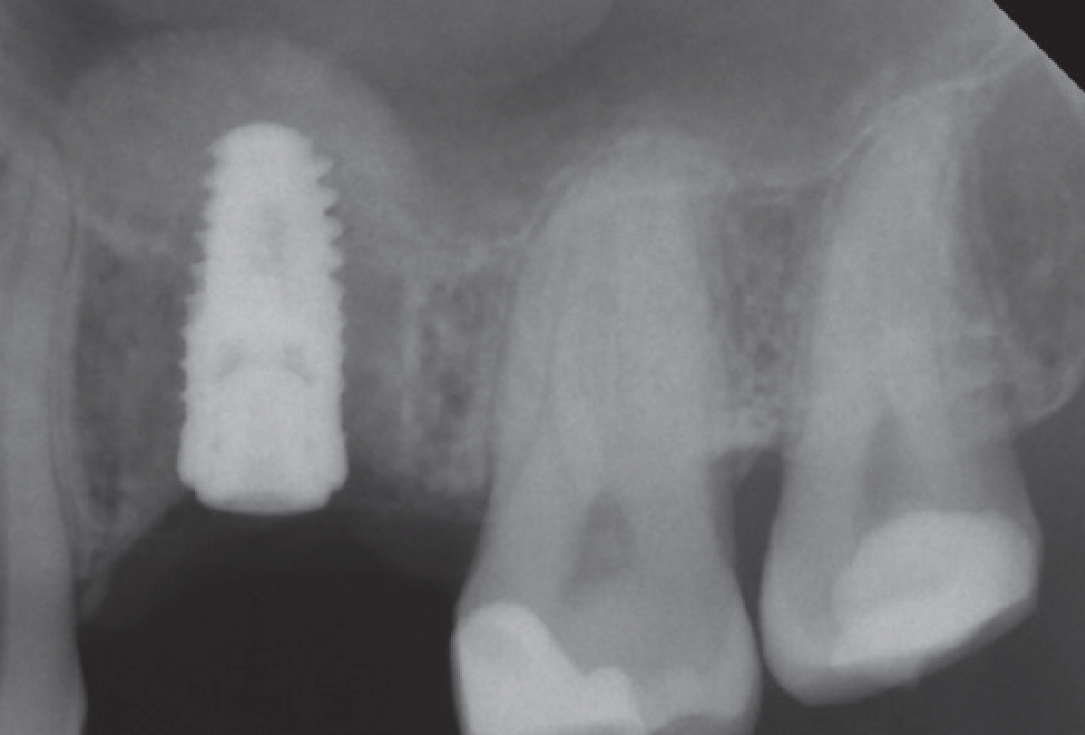

10/10 - X-ray control clearly showing the inserted maxresorb® injectInternal sinus lift with maxresorb® inject - case Dr. Frank Kistler

Preoperative Ortopantomogram of the teeth planned for extraction